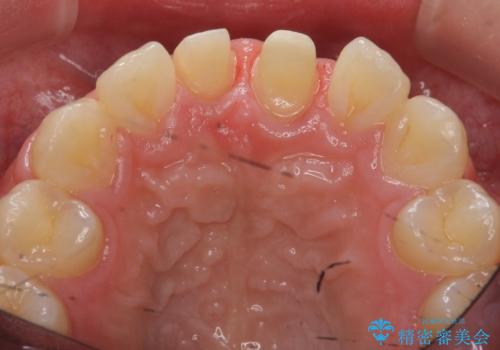

- 前歯の突出を主訴に来院。

矯正治療は絶対したくないとのことでした。

矯正治療をするメリット(神経を取らずに済む、歯を削らずに済む、セラミックを入れずに済む、歯ぐきのラインが整う)をお話しましたが、希望されませんでした。

部分矯正なども提示しましたが、早く治すセラミック治療を選択されました。

前歯の角度や歯ぐきのラインに差が大きかったため、やむなく神経をとり、歯ぐきの手術を行い出来るだけ歯ぐきのラインを整えるようにしました。

手術をしなければ左上1番の歯ぐきのラインは左上2番よりも下にきてしまい、長さの短い歯になってしまうところでした。